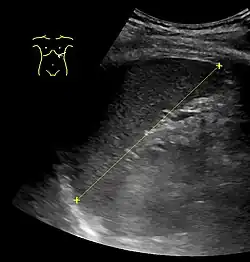

Maximum dimension of the spleen on abdominal ultrasonography.

The standard system for classifying splenomegaly on radiography is:[3][4]

• Normal (not splenomegaly): the largest dimension is less than 11 cm

• Moderate splenomegaly: the largest dimension is between 11 and 20 cm

• Severe splenomegaly: the largest dimension is greater than 20 cm